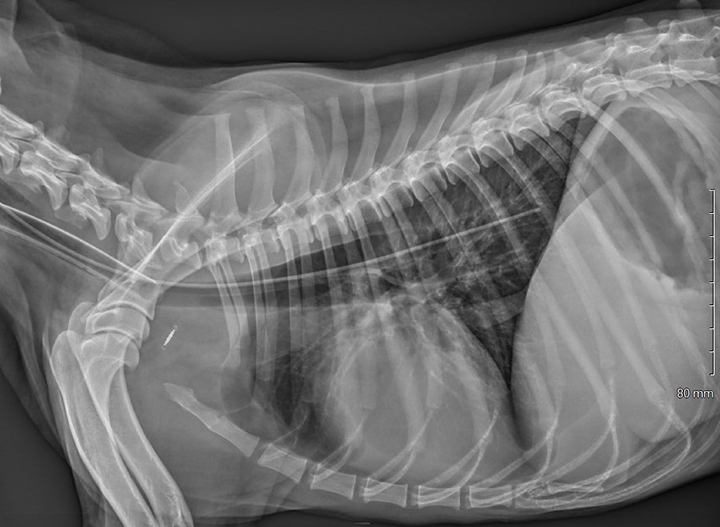

How to unclog a feeding tube in a dog VETgirl Veterinary Continuing